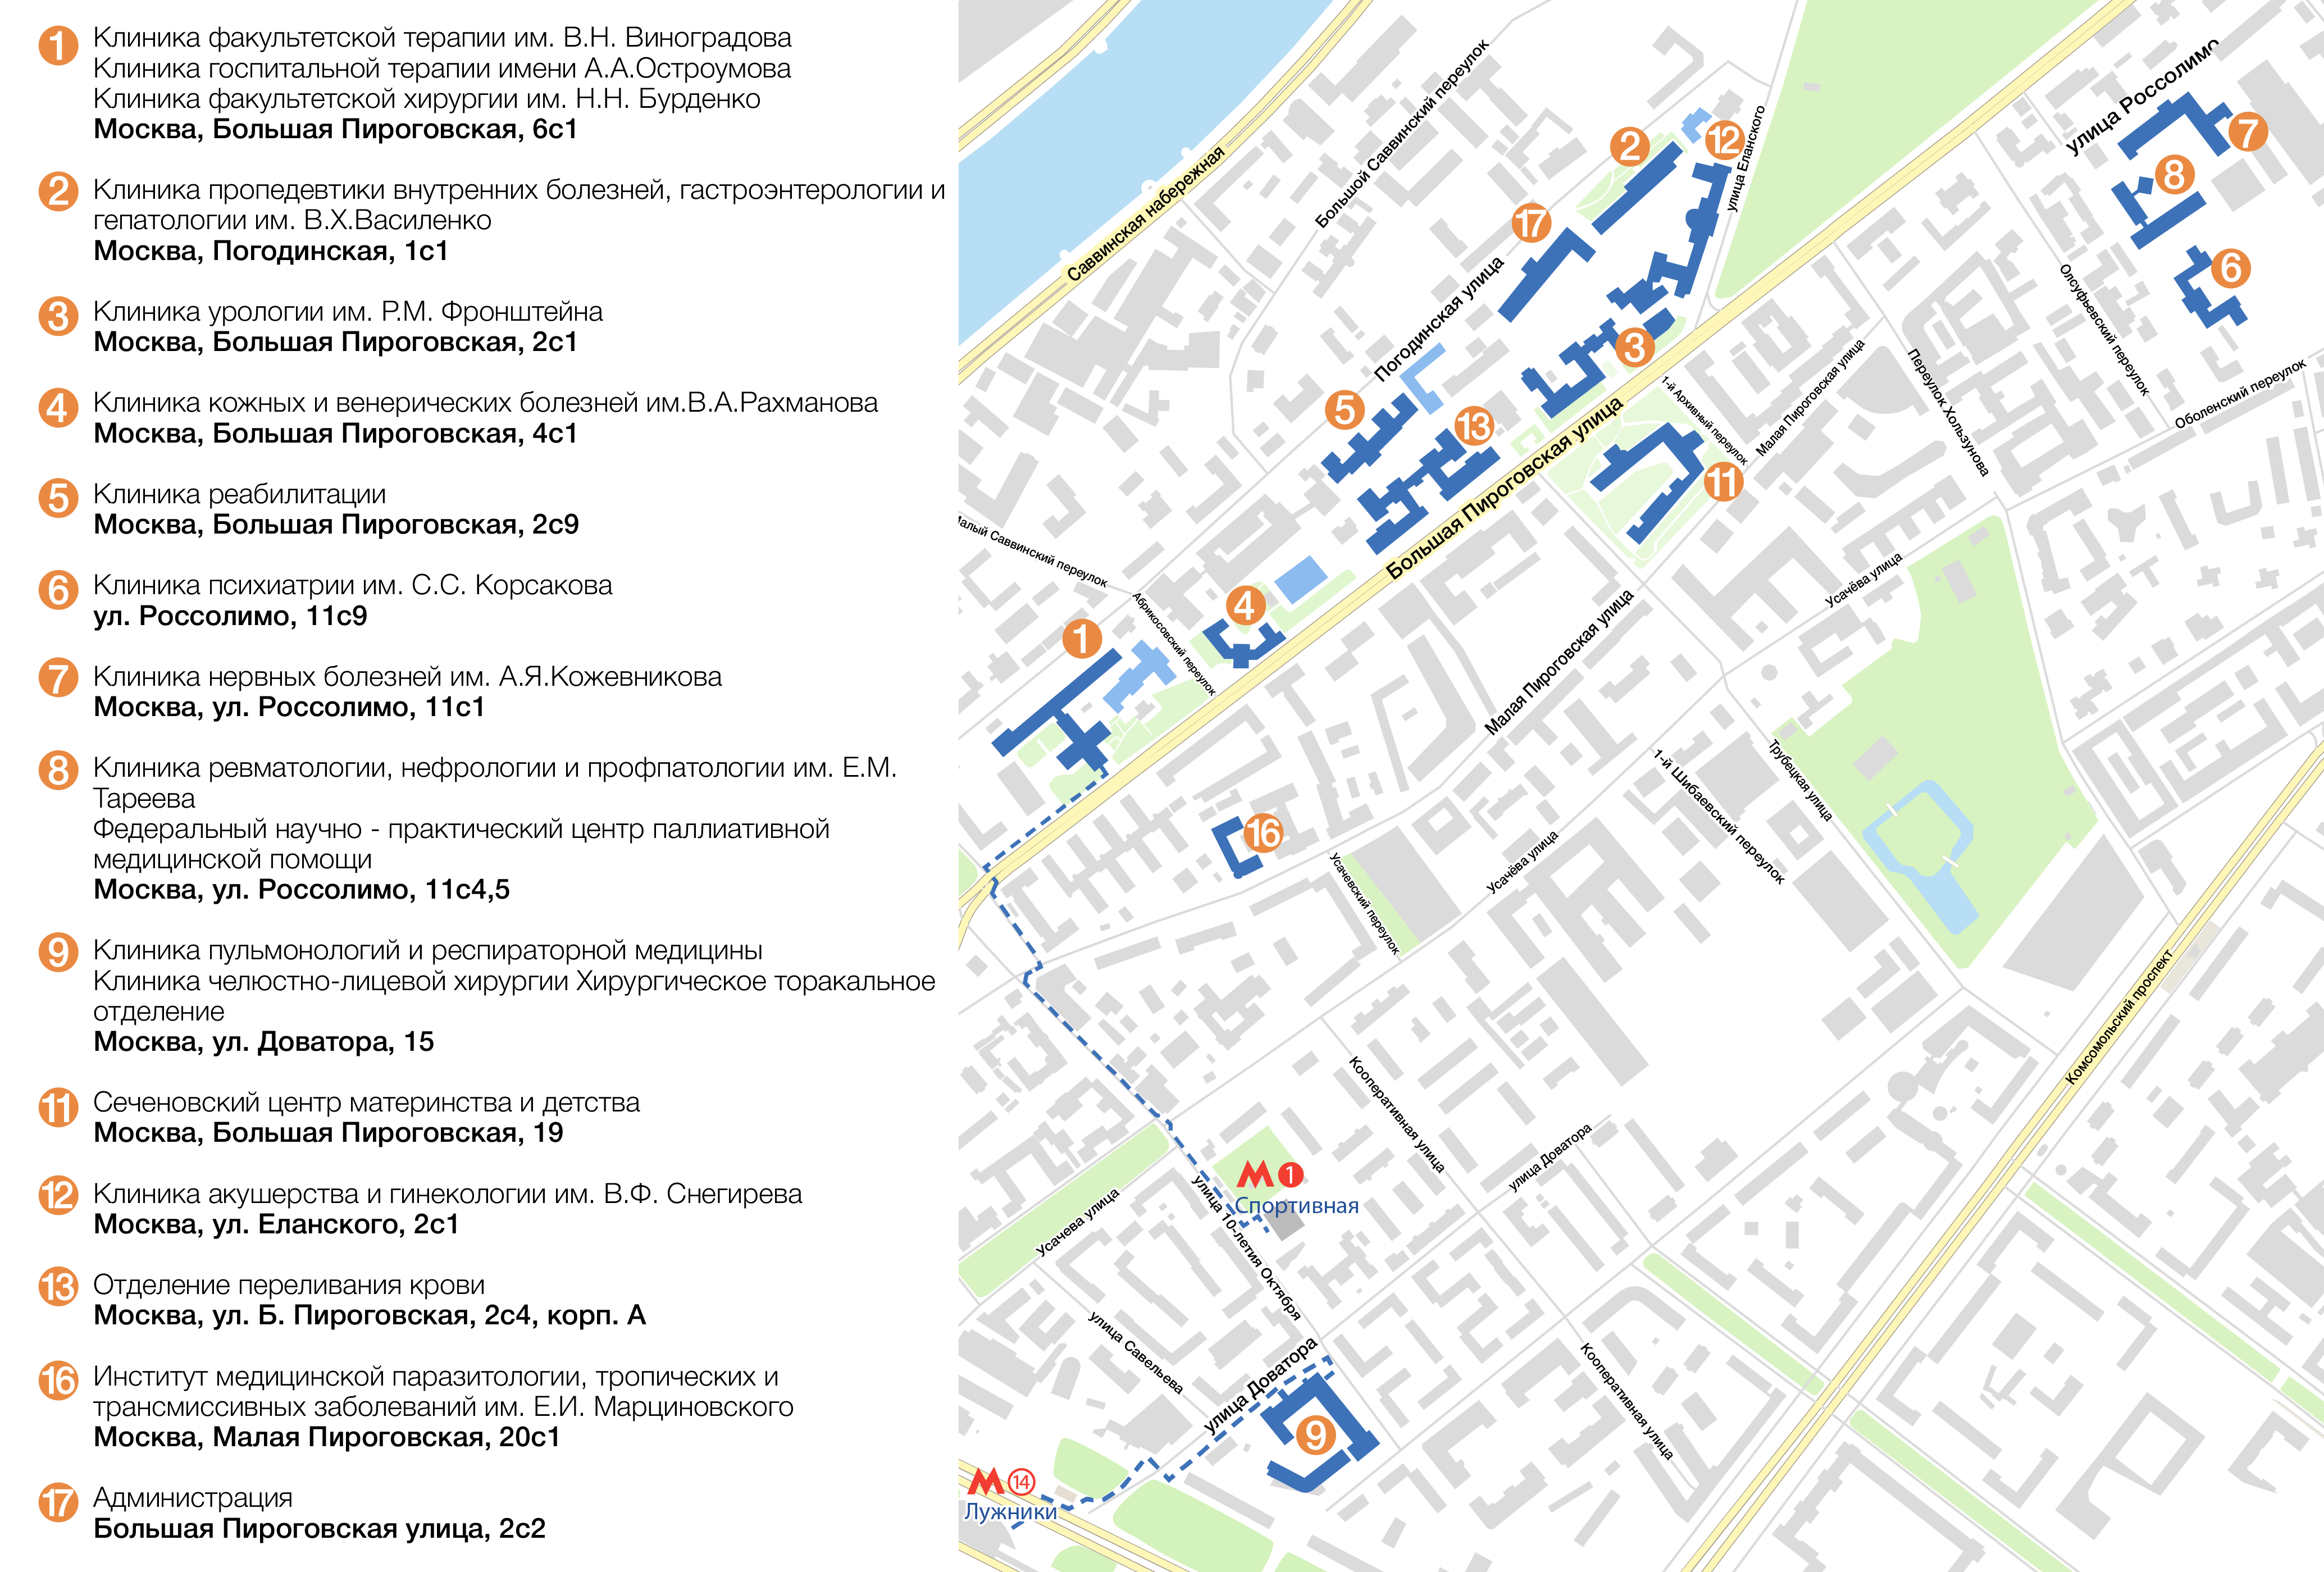

Адрес: Москва, ул. Больщая Пироговская дом 6 Университ...